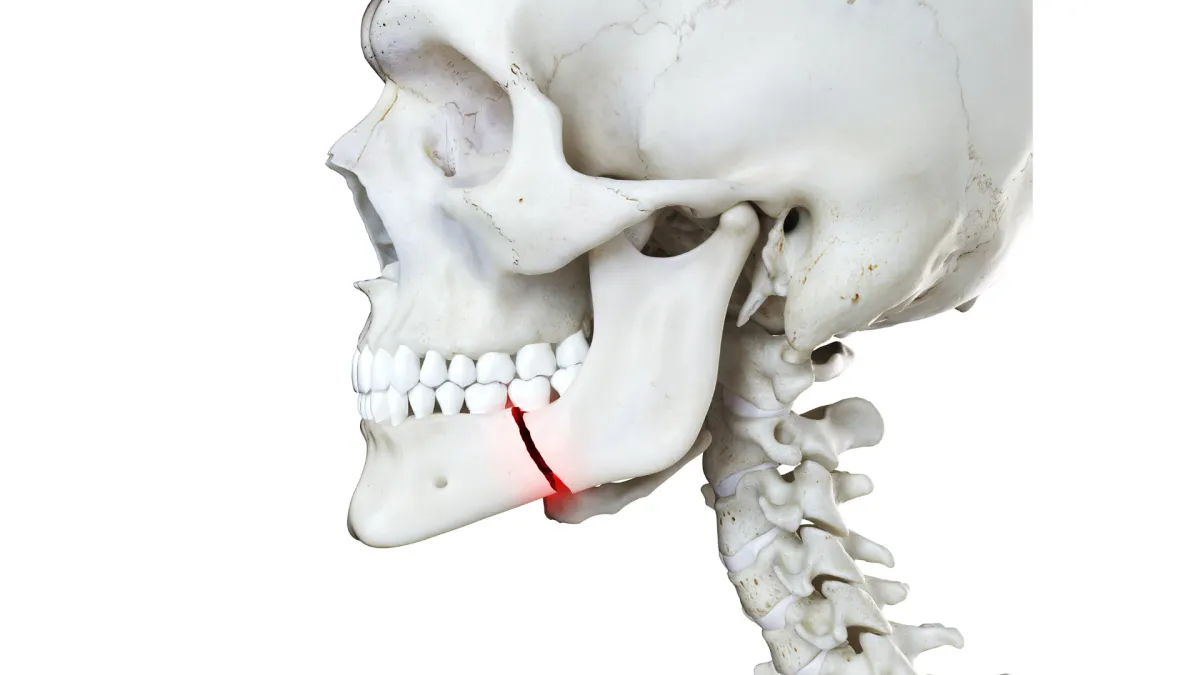

#9 - Injured Your Jaw

A broken jaw is no fun. Basically, there’s nothing you can do for this other than take some over the counter painkillers and put some ice on it until you can get to the ER.